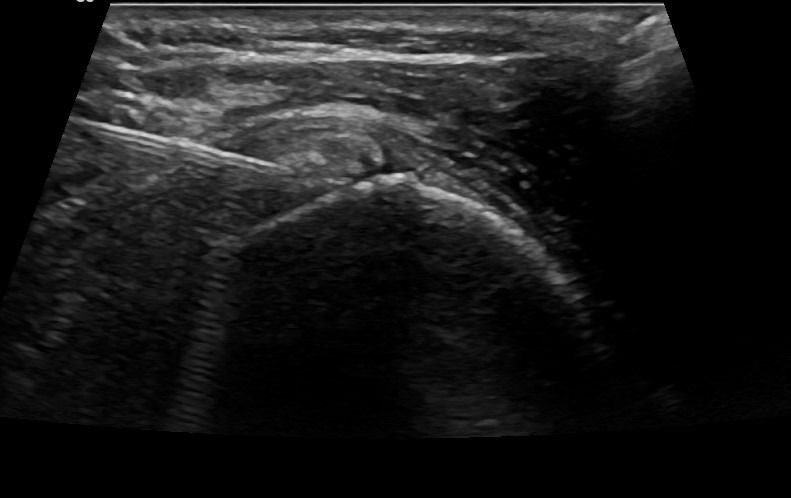

During Barbotage treatment, under local anesthesia and through a minimally invasive approach, calcifications are flushed with saline, and an anti-inflammatory drug is injected into the subacromial-subdeltoid bursa.

Thanks to ultrasound guidance, Barbotage is an effective and entirely safe procedure. The use of ultrasound ensures both the avoidance of vital structures, such as vessels and nerves, and the targeted injection of the therapeutic substance precisely where it is needed at the site of calcifications.

In contrast to blindly administered injections without ultrasound guidance, Barbotage has higher efficacy as it allows for targeted flushing of calcifications.